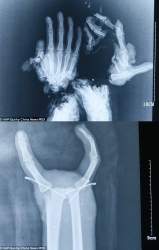

レントゲンでも結構グロいな上…

これ並べて撮るレントゲン技師すげぇ

分解されてても中の骨がどうなってるか

確認する為に分離した方もレントゲン撮ったのかな…

中国湖南省の工場で、18歳くらいの作業員(Wang Jinさん)がハンマー機械に両手を巻き込まれる。

手首から先が切断寸前、指は複数壊滅。

病院で9時間以上の手術。壊れた指は諦めて、使える親指+小指や人差し指を移植・再固定して「2本指の機能的手」にした。

結果、物を掴む・持つ基本動作は回復。術後2週間で指を曲げられるようになったらしい

上の画像見るに両手が粉々になったのか

>左手はこれレントゲン撮る意味ある?

ある

というかグッチャグチャでもうわからないからレントゲンでとりあえず現状把握しないと計画も立てられない